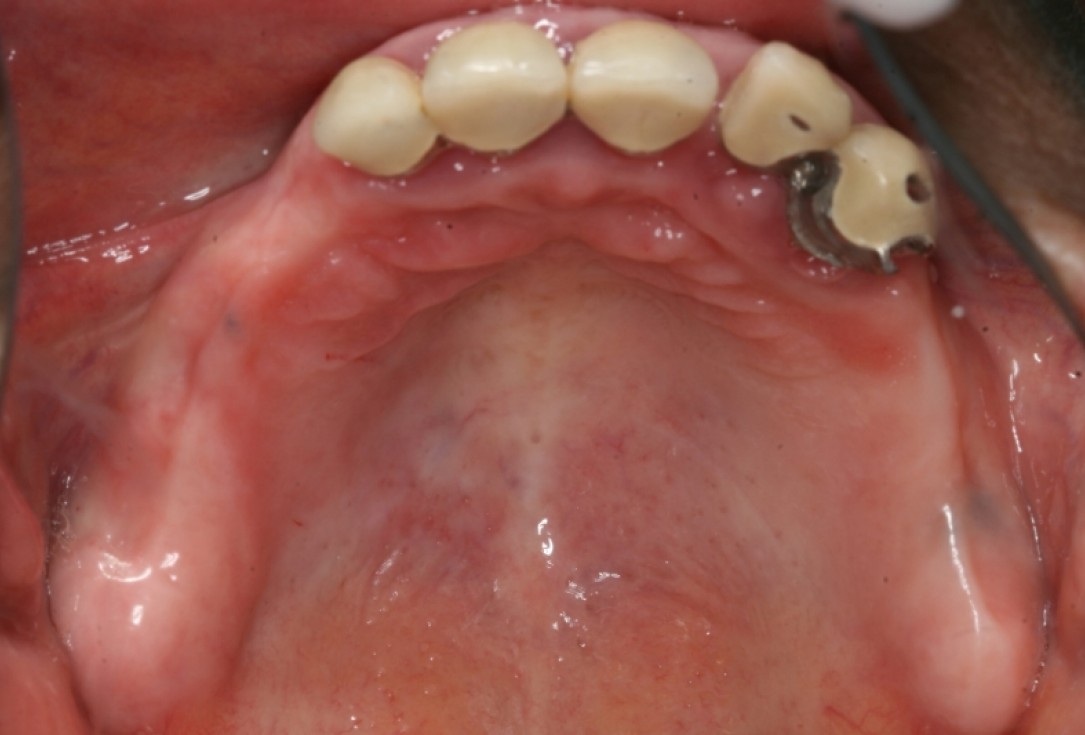

Initial situation pre-op: Central incisors with mobility 3